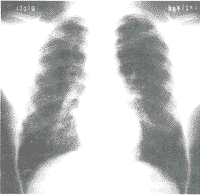

[例1]男,19岁,康定县时济乡农民。1994年6月至7月从事金矿放炮及放炮后安放排气管工作仅1个月。粉尘(含炸药烟尘)浓度大,洞内粉尘及烟雾弥漫,对面不见人,多以口罩防护。1997年10月因感冒后干咳,到甘孜州人民医院检查,X线胸片疑为Ⅱ期尘肺。1998年11月10日因患感冒、干咳加重住本院诊治。胸片发现双肺广泛圆形小阴影,以p影为主,右上中下及左中达2级密集度(图1)。体格检查血常规,肝、肾功能及血沉均正常,24小时痰浓缩查抗酸杆菌(-),PPD皮试(-),细胞免疫功能正常,抗核抗体、类风湿因子、C反应蛋白、补体等指标均正常,仅免疫球蛋白IgA增高,临床及实验室检查排除肺结核及结缔组织变态反应疾病,诊断为Ⅱ期尘肺。

图1 双肺广泛圆形小阴影,以p影为主,右上中下及左中达2级密集度